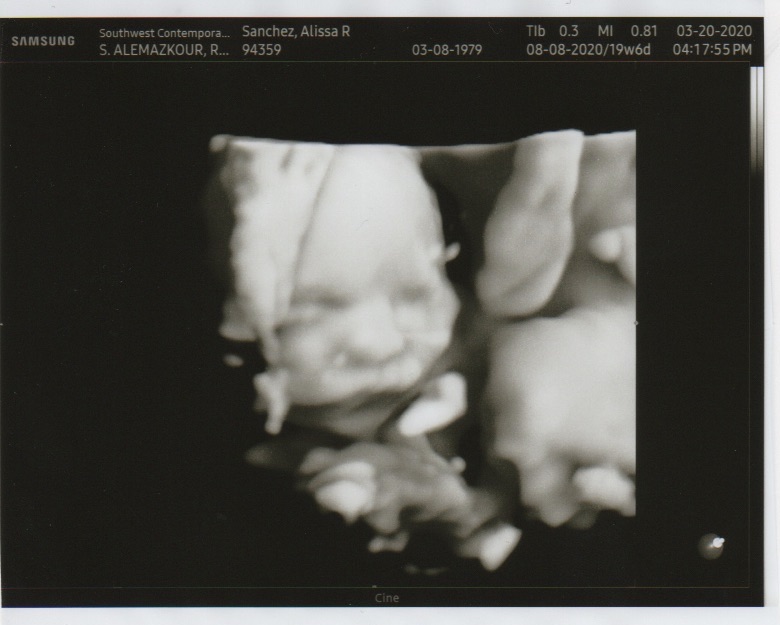

Below you will see a few photos of our gorgeous baby GIRL that we are expecting at the beginning of August!

She is our rainbow baby...meaning, she is our rainbow after a storm.

I will explain once you enjoy her most recent ultrasound photos!

We feel so blessed and thankful to God that here we are expecting a healthy baby girl!